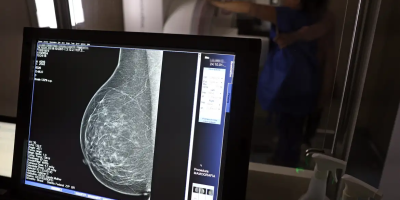

No mês de conscientização sobre o câncer de mama, um relatório destaca a importância de acesso igualitário ao rastreamento e tratamento da doença. Segundo o Atlas da Radiologia no Brasil, do Colégio Brasileiro de Radiologia e Diagnóstico por Imagem (CBR), o acesso aos mamógrafos ainda é um desafio.

Imagem: José Cruz / Agência Brasil

O país tem 6.826 equipamentos registrados, sendo 96% em funcionamento. Metade deles está disponível no Sistema Único de Saúde (SUS), responsável por atender 75% da população. Isso equivale a 2,13 mamógrafos por 100 mil habitantes dependentes do SUS.